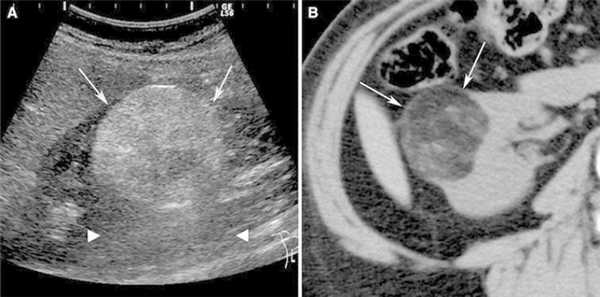

Для демонстрации возможностей метода химиоэмболизации с двухсторонним поражением почек приводим клинический случай лечения пациентки К., 35 лет.

Из данных анамнеза: пациентка считает себя больной с сентября 2009 года. Диагноз выставлен на основании УЗИ, КТ и ангиографии: размеры опухоли правой почки 19,5×9,4×11,2 см, в левой почке — 7,1×8,3×6,2 см.

Диагноз: Рак правой почки T 3 N 1 M 1 IV St . Mts в ниж ний полюс левой почки.

Проведено лечение: 1 курс иммунохимиотерапии без особого эффекта. Следующим этапом провели эмболизацию опухоли правой почки и селективную эмболизацию опухоли нижнего полюса левой почки (рис. 1, 2) с последующей нефрэктомией правой почки (рис. 3) с целью циторедукции с последующей химиоиммунотерапией. Пациентка в период 2010-2012 гг. получила таргетную терапию препаратом Сорафениб по 400 мг 2 раза в сутки в течение двух лет, далее у нее развилась непереносимая токсичность препарата, и лечение было остановлено. В настоящее время при контрольном обследовании данных за прогрессирование не выявлено, на контрольной ангиографии левой почки опухоль в динамике без признаков реваскуляризации и роста (рис. 4).